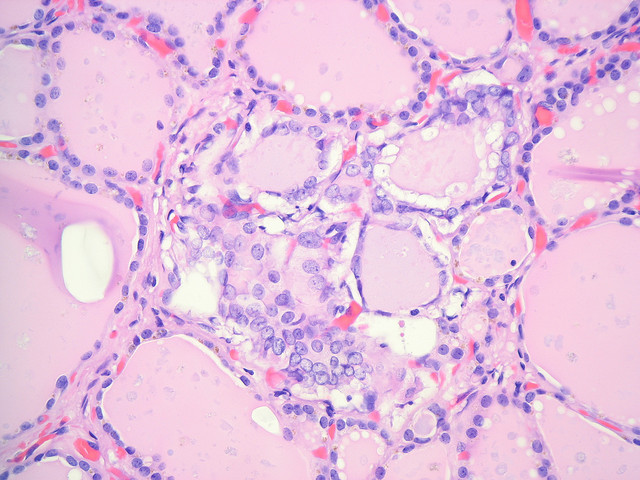

Ультразвуковое исследование щитовидной железы

Благодаря тому, сколько стоит УЗИ щитовидной железы (а стоит оно недорого), можно определить участки неоднородности ткани этого органа очень легко. Их размер может составлять до 3 мм. Задача такого обследования – обнаружить пациентов, которым требуется проведение тонкоигольной биопсии. При небольшом узле диагностика будет предложена через год, тогда пациент и сможет узнать, сколько стоит УЗИ щитовидной железы. Ведь проводиться исследование должно на том же аппарате. Это даст возможность увидеть рост, если он есть.